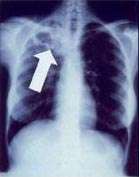

Chest X-ray and CT

In active pulmonary TB, infiltrates or consolidations and/or cavities are often seen in the upper lungs with or without mediastinal or hilar lymphadenopathy or pleural effusions ( tuberculous pleurisy). However, lesions may appear anywhere in the lungs. In disseminated TB a pattern of many tiny nodules throughout the lung fields is common - the so-called miliary TB. In HIV and other immunosuppressed persons, any abnormality may indicate TB or the chest X-ray may even appear entirely normal.

Abnormalities on chest radiographs may be suggestive of, but are not necessarily diagnostic of, TB. However, chest radiographs may be used to rule out the possibility of pulmonary TB in a person who has a positive reaction to the tuberculin skin test and no symptoms of the disease.

Cavitation or consolidation of the apexes of the upper lobes of the lung or the tree-in-bud sign[7] may be visible on an affected patient's chest X-ray.[1] The tree-in-bud sign may appear on the chest CTs of some patients affected by tuberculosis, but it is not specific to tuberculosis.[7]